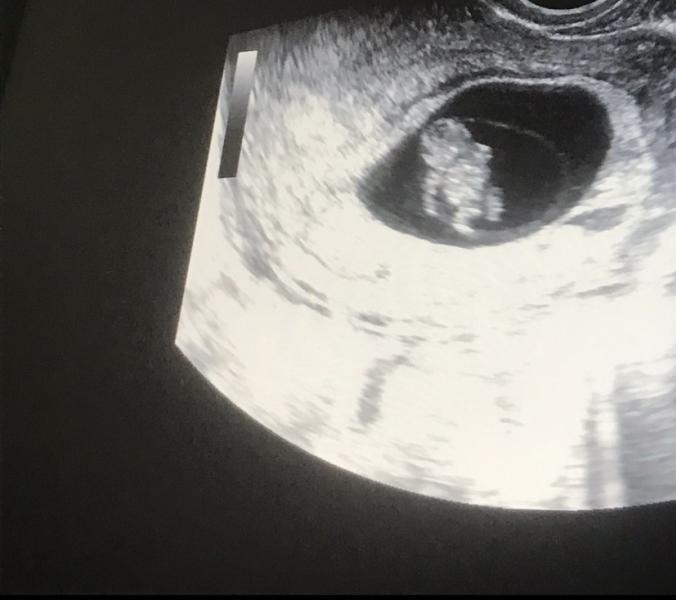

Срок беременности 8.3 недели: как развивается малыш и когда ждать следующего УЗИ? Дата 8.06.2022

💕Срок акушерский 8.3💕

Маленький человечек 🙈

Ну прямо космонавт в космосе )